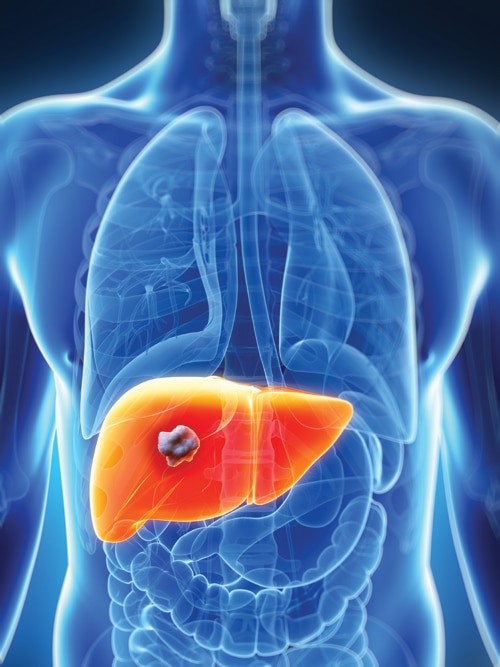

Η ηπατική νόσος είναι ένας σιωπηλός δολοφόνος. Οι περισσότεροι άνθρωποι δεν γνωρίζουν ότι έχουν ηπατικό πρόβλημα έως ότου αυτό προχωρήσει και αναπτύξουν ουλές στο ήπαρ, κίρρωση του ήπατος και, σε σοβαρές περιπτώσεις, ηπατική ανεπάρκεια και θανατηφόρο καρκίνο. Οι επιπλοκές της, ωστόσο, δεν περιορίζονται στην ηπατική νόσο. Συνδέεται στενά με διάφορες άλλες καρδιομεταβολικές παθήσεις, όπως ο διαβήτης τύπου 2 και οι καρδιαγγειακές παθήσεις. Ως απάντηση στην COVID-19, ο ξενιστής (άνθρωπος) αναπτύσσει μια ανοσολογική απάντηση, η λεπτή ισορροπία της οποίας καθορίζει την πορεία της νόσου. Η σοβαρή COVID-19 σχετίζεται με επιδεινωμένες ανοσολογικές και υπερφλεγμονώδεις αποκρίσεις και τα φλεγμονώδη μακροφάγα μπορούν να προκαλέσουν καταιγίδα κυτοκινών που οδηγεί σε ιστική βλάβη. Μια νέα μελέτη από ερευνητές του Ινστιτούτου Ιατρικής Έρευνας Westmead του Πανεπιστημίου του Σίδνεϊ ανακάλυψε πώς η COVID-19 αυξάνει τον κίνδυνο λιπώδους ηπατικής νόσου και πώς το τελευταίο αυξάνει τη σοβαρότητα της COVID-19, βοηθώντας στην ανάπτυξη πιθανών θεραπειών για τους ασθενείς αυτούς.

Ο Δρ Jawaher Alharthi, πρώτος συγγραφέας της εργασίας αυτής, δήλωσε: “Η σχέση μεταξύ της λιπώδους νόσου του ήπατος και της COVID-19 θεωρείται λίγο μυστήριο, καθώς δεν γνωρίζουμε πώς και γιατί οι δύο ασθένειες αυξάνουν τον κίνδυνο η μία της άλλης. Η ερευνητική μας ομάδα με επικεφαλής τον καθηγητή Mohammed Eslam διεξήγαγε μια μεγάλη και λεπτομερή γενετική και μοριακή μελέτη και εντόπισε ότι το γονίδιο που ονομάζεται MBOAT7 σχετίζεται με τη σοβαρότητα τόσο της λιπώδους νόσου του ήπατος MAFLD όσο και της COVID-19”. “Αυτό το γονίδιο, παίζει σημαντικό ρόλο στη ρύθμιση των ανοσολογικών και φλεγμονωδών αποκρίσεων κατά της COVID-19. Μια διαταραχή στη δραστηριότητα του γονιδίου MBOAT7 θα μπορούσε να αυξήσει τις πιθανότητες αύξησης της παραγωγής κυτταροκινών και της βλάβης των ιστών και της ηπατικής νόσου”, δήλωσε ο Δρ Alharthi. Το επιγονιδίωμα είναι ένα σύνολο δεικτών που καθορίζει όχι μόνο τη γονιδιακή έκφραση, αλλά και τα ίδια τα γονίδια και επηρεάζεται από το περιβάλλον, τη διατροφή και τις ορμόνες. “Είναι ενδιαφέρον ότι εντοπίσαμε επίσης ότι η διακοπή του MBOAT7 μπορεί να “προ-προγραμματίσει” το επιγονιδίωμα των κυττάρων και να τα προετοιμάσει ώστε να ανταποκριθούν έντονα ακόμη και σε μια ασθενή διέγερση κατά της COVID-19 που τελικά αυξάνει τη βλάβη των ιστών”.